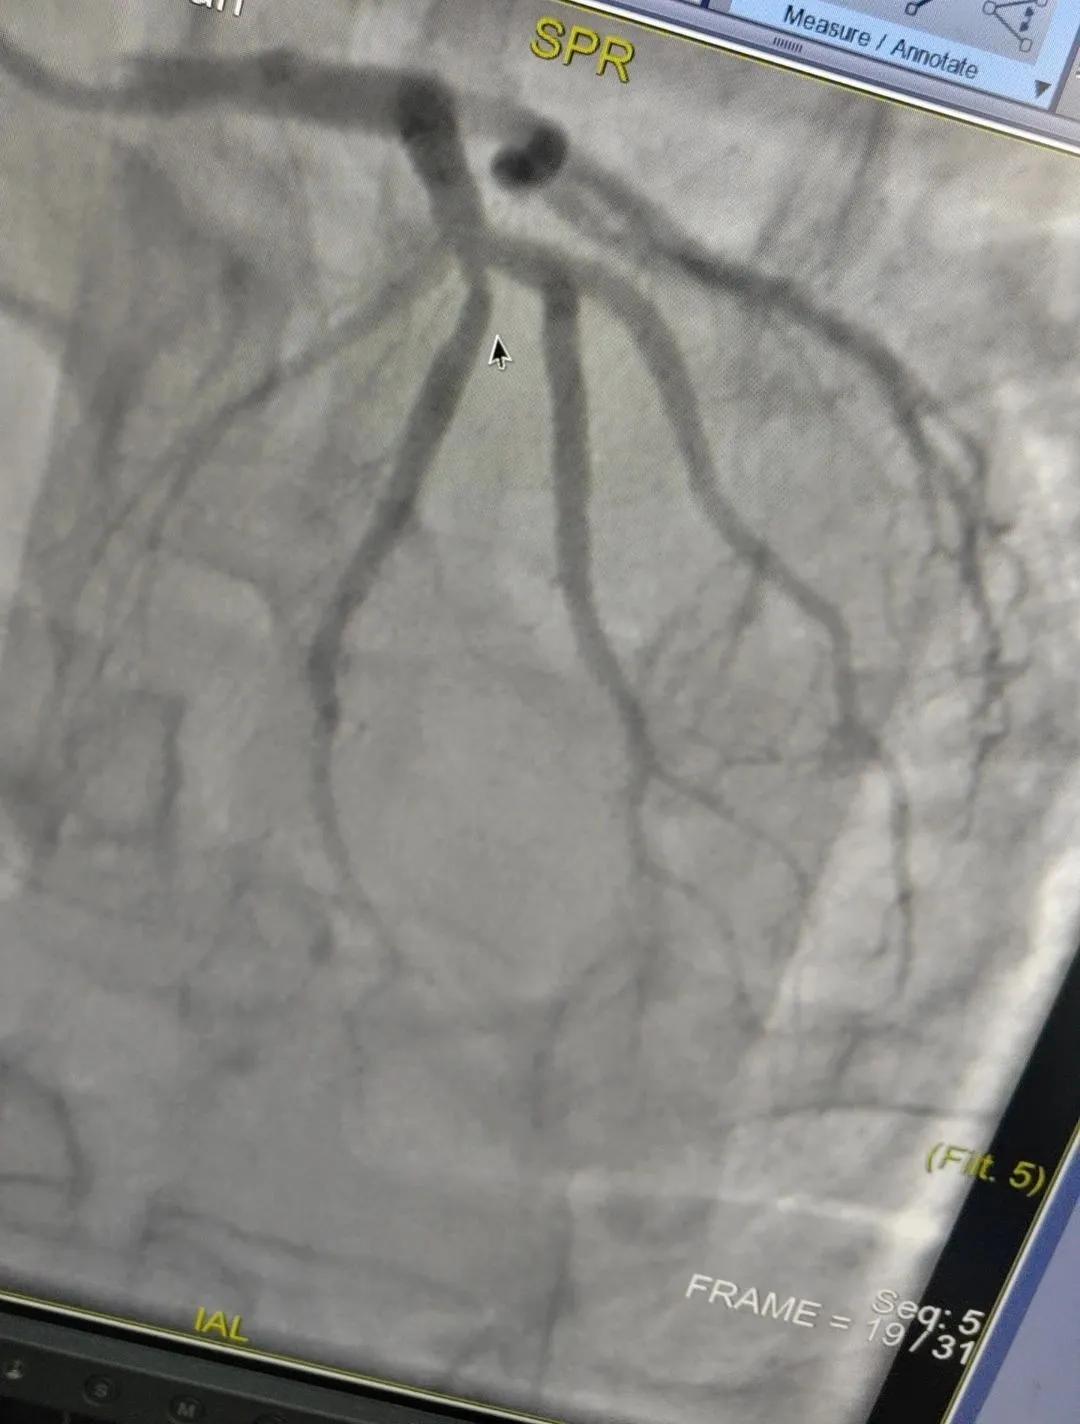

術(shù)中心血管造影顯示:LAD中段發(fā)出D1處可見約50%節(jié)段性狹窄,RCA中段狹窄約40%,PLA可見約70%狹窄病變。

腦血管造影顯示:左側(cè)頸內(nèi)動脈嚴(yán)重遷曲,左側(cè)大腦前動脈未顯影,左側(cè)大腦中動脈M1中段以遠(yuǎn)未顯影,M1近段串珠樣嚴(yán)重狹窄,顱底可見少量煙霧血管,后交通動脈未開放;右側(cè)頸內(nèi)動脈嚴(yán)重遷曲。右側(cè)大腦前動脈A1段嚴(yán)重遷曲。